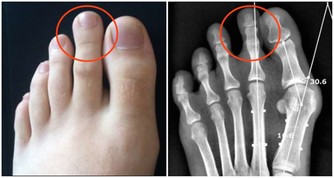

▼有便秘問題的朋友們大部分也會因為不良排便習慣而面對長痔瘡的困擾,有些人只是在排便時輕微出血;但嚴重者分分鐘會因為這小小一顆「痘痘」而痛苦不堪,連行動都成問題。如果你真的不想要因為痔瘡問題去動手術的話,那就趕緊用蹲姿上廁所!